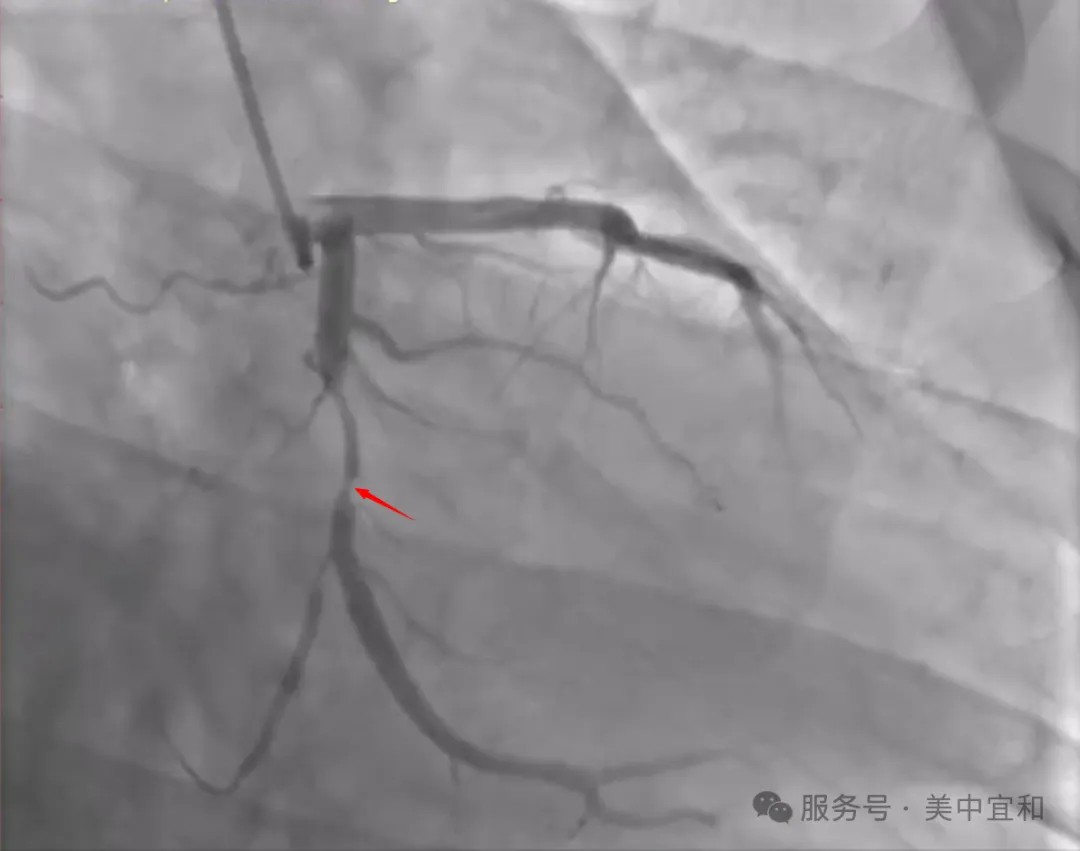

时间倒溯至1月前,从外省专程前来我院就诊的张先生,是内科主任颜教授的“老患者”,颜主任刚刚帮王先生做完冠脉造影手术,在出院前,张先生得知院区已开设眼科,抱着“很方便”的心态,咨询个案专管赵老师能否“顺便”到眼科就诊,复查一下他的“陈年旧疾”。

但是,王先生刚刚做完冠脉造影手术,还在后续用药和随访期间,到底能否手术治疗眼疾,需要根据术后恢复情况择期进行!